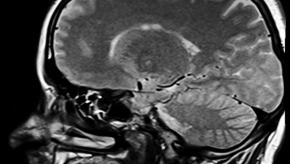

Read ArticleTwo-Fold Increase of Demyelinating Diseases with TNF Inhibition

Despite the potential contributory role of TNF in the pathogenesis of multiple sclerosis, several trials have shown that TNF inhibitor (TNFi) use may lead to worsening of MS, optic neuritis and other demyelinating disorders.